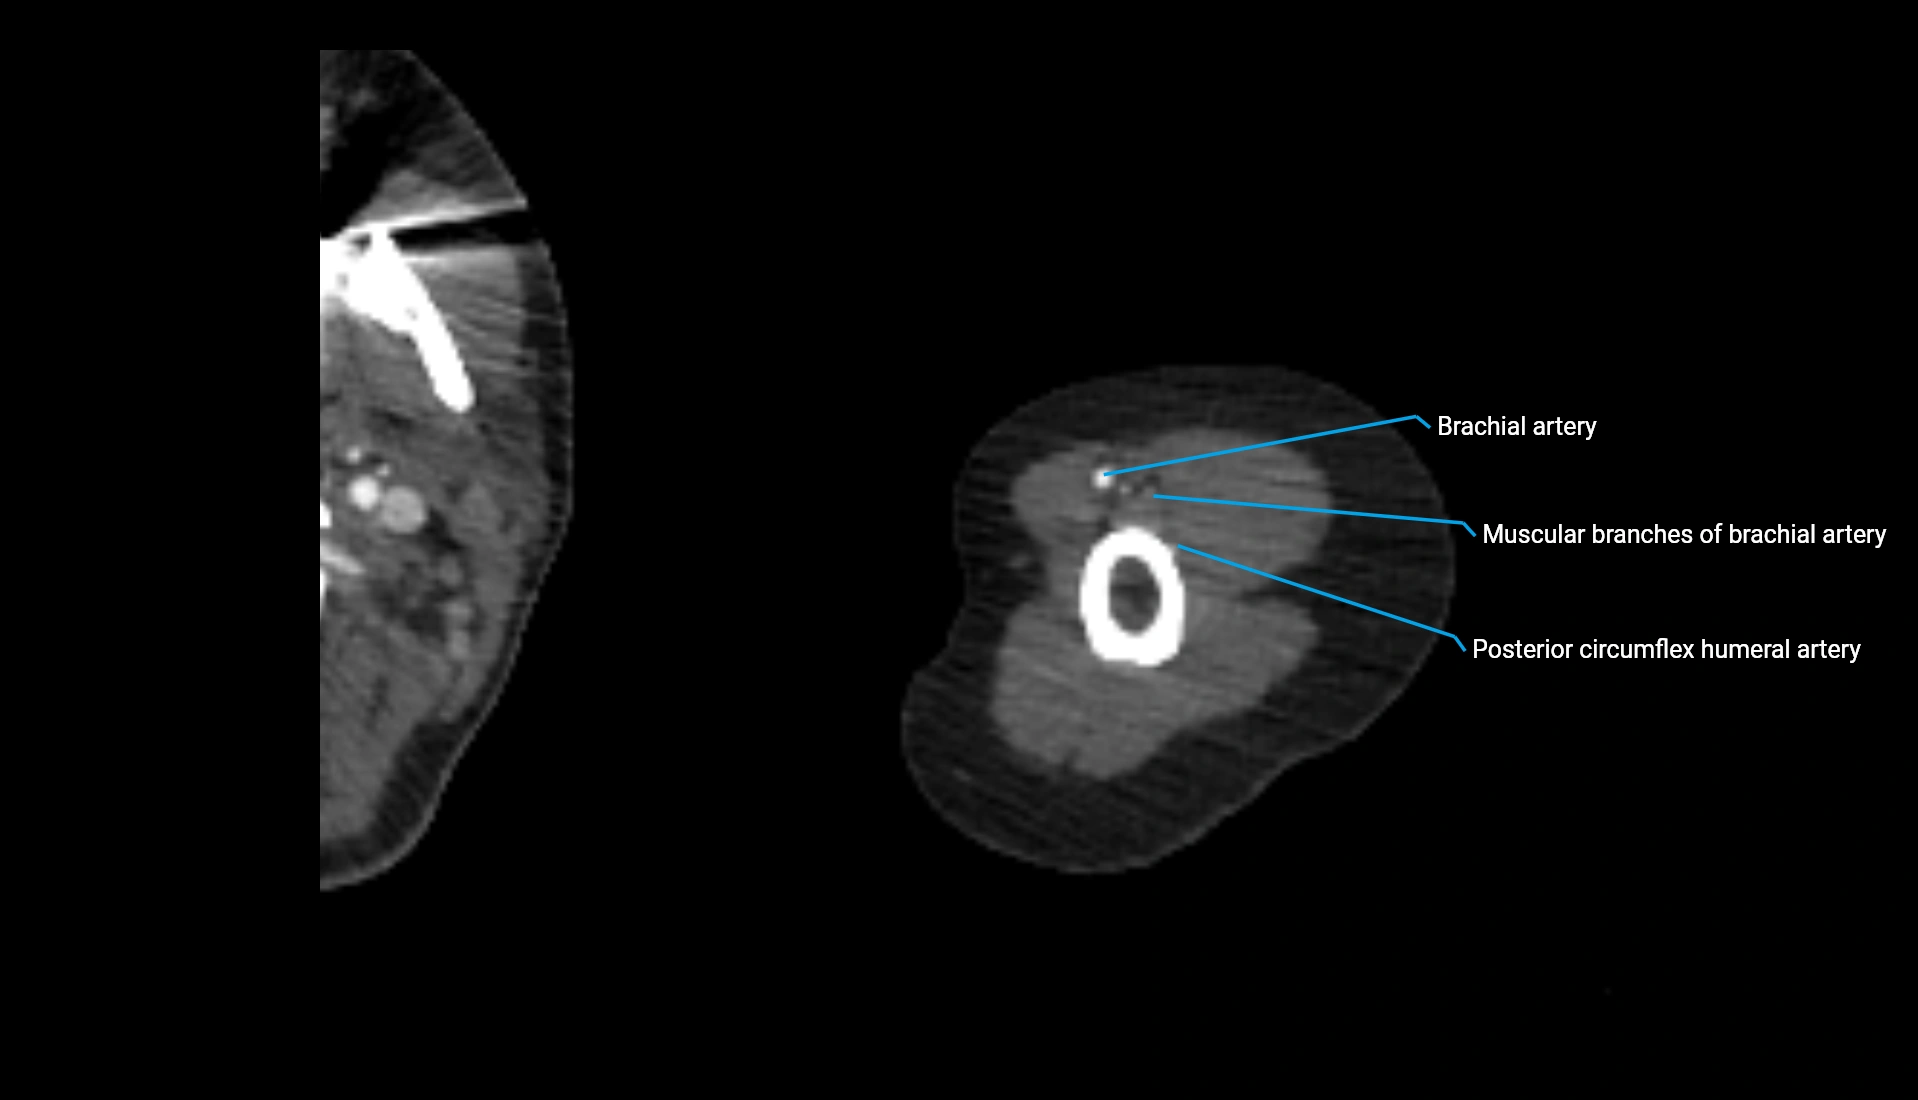

CT Appearance

Non-Contrast CT:

• Cortex: High-density, sharply defined

• Subchondral bone: Dense cancellous matrix

• Articular surface: Smooth concave contour articulating with the capitellum

• Excellent for evaluating bone integrity, alignment, and subtle fractures